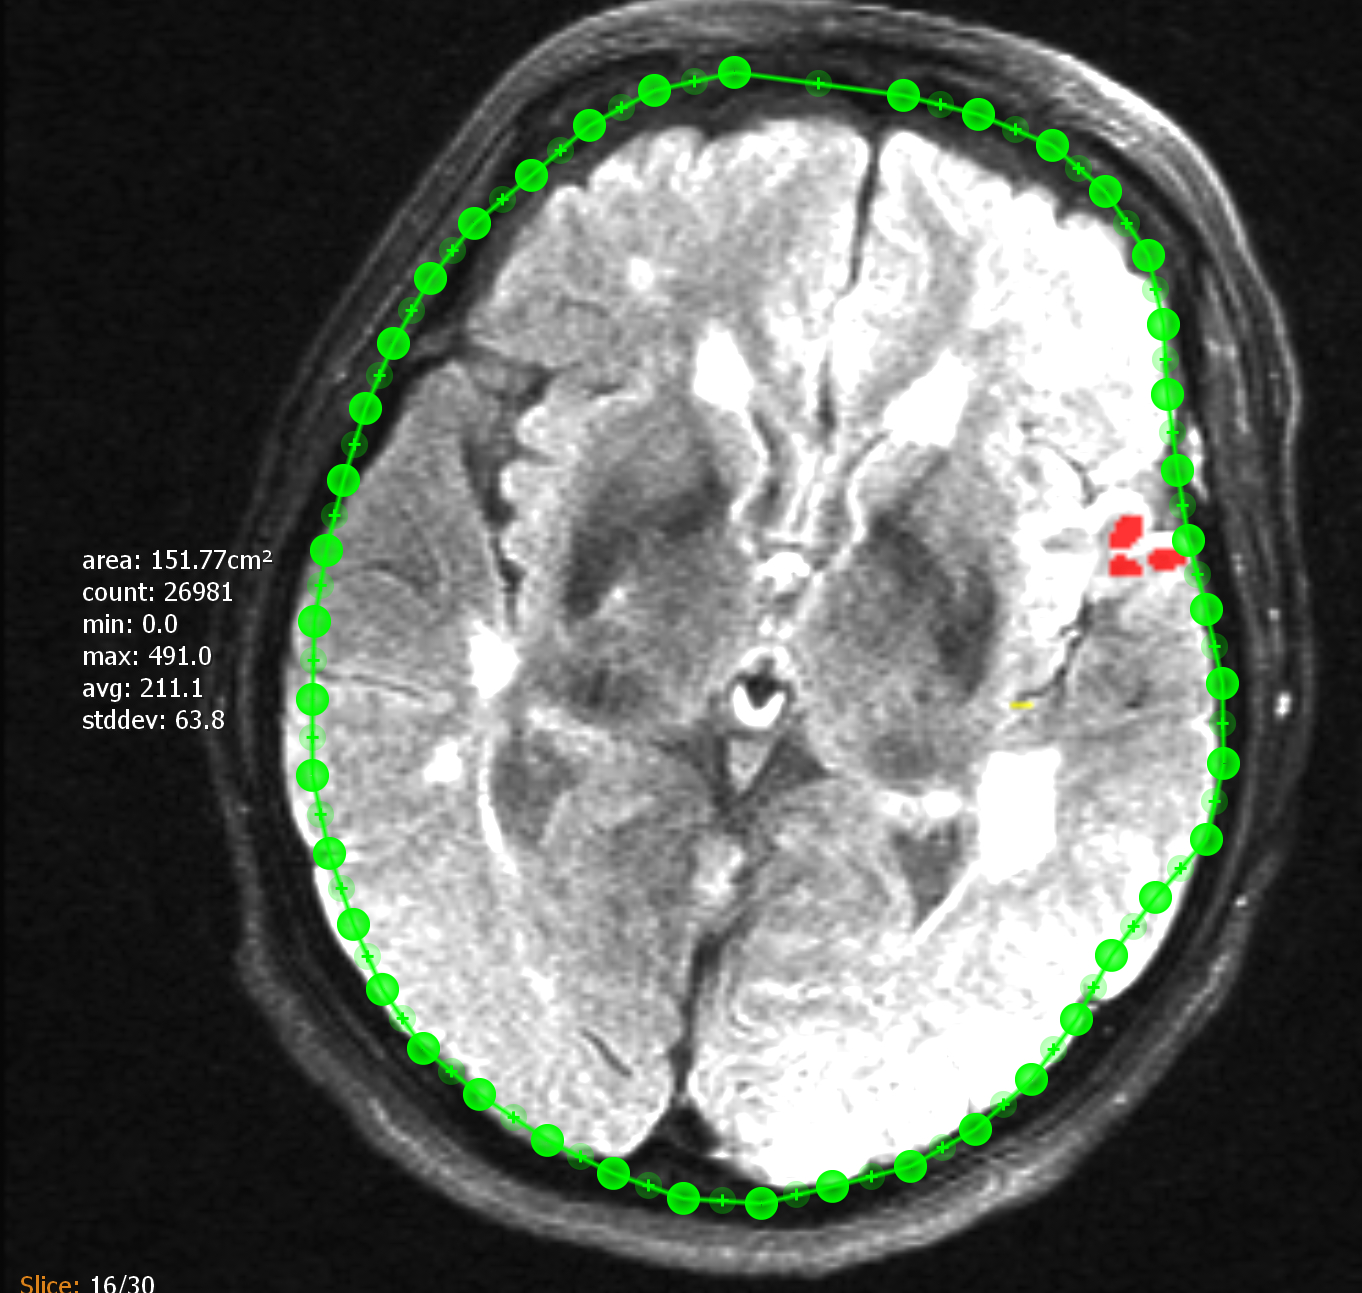

You can use the "Segmentation"tool to insert a manual segmentation into a layered image. After activating, circle the object to be segmented with your finger. The annotation can then be adjusted. The segmentation points can be easily moved or deleted with double tap. New points can be added by' +'. On the side of the segmentation there is an additional information text which contains the following calculated values for the pixels in the segmentation:

-

area: Segmented area (optional if image spacing is correct).

-

count: Number of pixels inside the ROI.

-

min: Smallest selected grayscale value.

-

max: Biggest selected grayscale value.

-

avg: Average grayscale value of all selected pixels.

-

stddev: Average spread of all grayscale values from the average grayscale value.